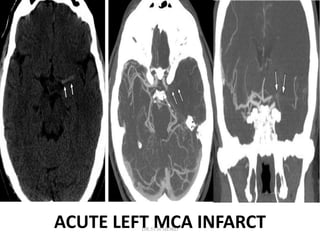

ACUTE LEFT MCA INFARCT

CT ANGIOGRAPHY

CT angiography typically involves a volumetric helical acquisition that

extends from the aortic arch to the circle of Willis.

• The examination is performed by using a time-optimized bolus of

contrast material for vessel enhancement.

• CT angiographic demonstration of a significant thrombus burden

can guide appropriate therapy in the form of intraarterial or

mechanical thrombolysis.

• Identification of carotid artery disease and visualization of the

aortic arch may provide clues to the cause of the ischemic event

and guidance for the interventional neuroradiologist